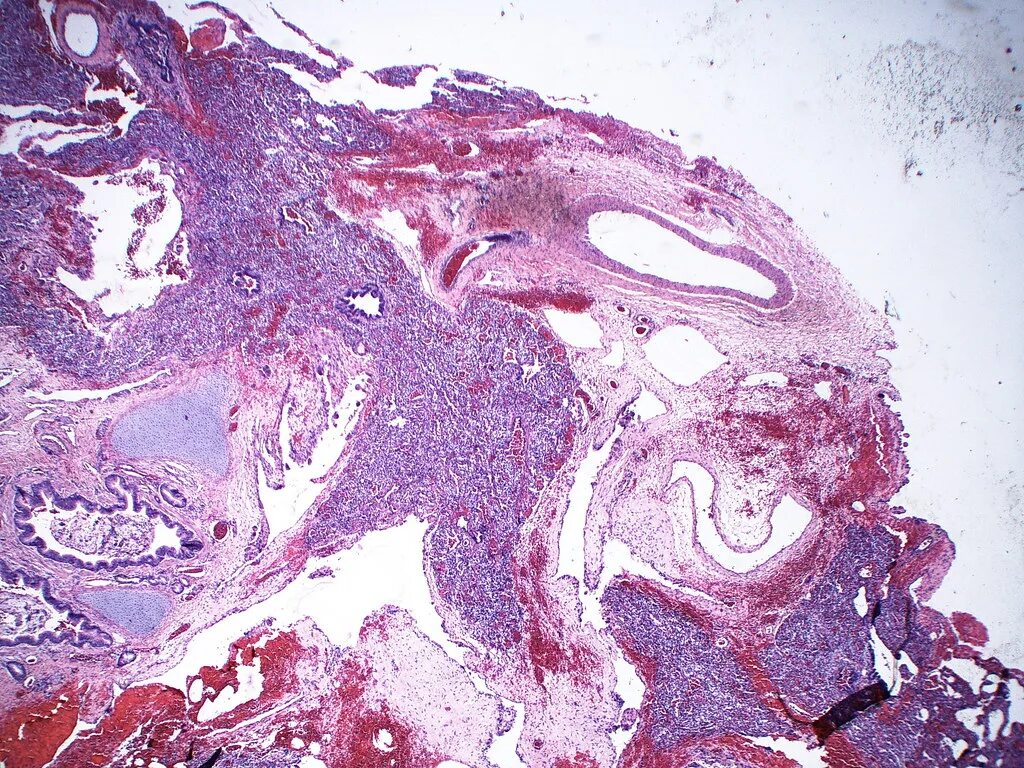

Серозный выпот